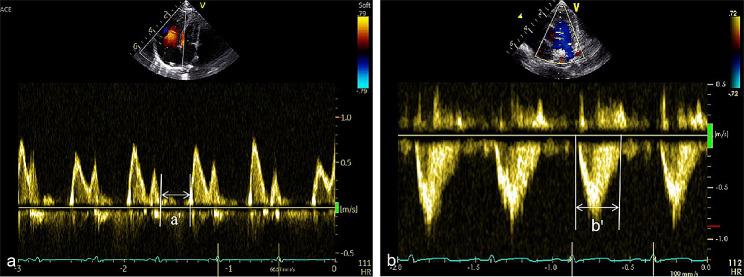

This retrospective study included infants with gestational age (GA) below 32 weeks, who were admitted to the neonatal intensive care unit(NICU). The detection rate of tricuspid regurgitation jet velocity (TRVJ), ventricular septal flattening, pulmonary artery widening, right ventricular dilation, and right atrial enlargement on the 7th day of life (DOL 7) were compared between BPD and non-BPD infants. Echocardiographic indices of the right ventricular function including tricuspid annular plane systolic excursion (TAPSE) and right ventricular index of myocardial performance (RIMP) were measured on 1 day of life (DOL 1)、on DOL 7 and on 14 day of life (DOL 14) respectively. The PLT parameters including the PLT count, mean platelet volume (MPV), platelet hematocrit (PCT) level, and platelet distribution width (PDW) were measured on the DOL 1,DOL 7, and DOL 14. Multivariate logistic regression was used to analyze the relationship between these parameters and BPD. Receiver operating characteristic curve analysis was performed to assess the predictive value of the right ventricular function indices and PLT parameters for BPD.

本回顾性研究纳入胎龄(GA)<32 周、入住新生儿重症监护病房(NICU)的患儿。比较 BPD 组与非 BPD 组患儿第 7 天(DOL 7)三尖瓣反流射流速度(TRVJ)、室间隔变平、肺动脉增宽、右心室扩张、右心房扩大的检出率。分别于生后第 1 天(DOL 1)、DOL 7 和第 14 天(DOL 14)测量右心功能超声心动图指标三尖瓣环平面收缩期位移(TAPSE)和右心室心肌做功指数(RIMP)。于 DOL 1、DOL 7 和 DOL 14 检测 PLT 参数,包括血小板计数、平均血小板体积(MPV)、血小板压积(PCT)水平和血小板分布宽度(PDW)。采用多因素 logistic 回归分析这些参数与 BPD 的关系。采用受试者工作特征曲线分析右心功能指标和 PLT 参数对 BPD 的预测价值。